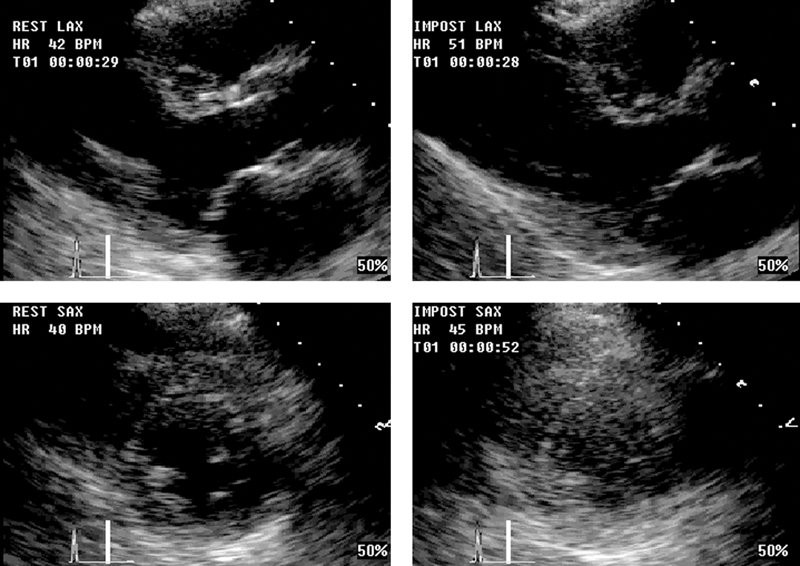

فحوصات تشخيصية لبعض امراض القلب والشرايين التاجية